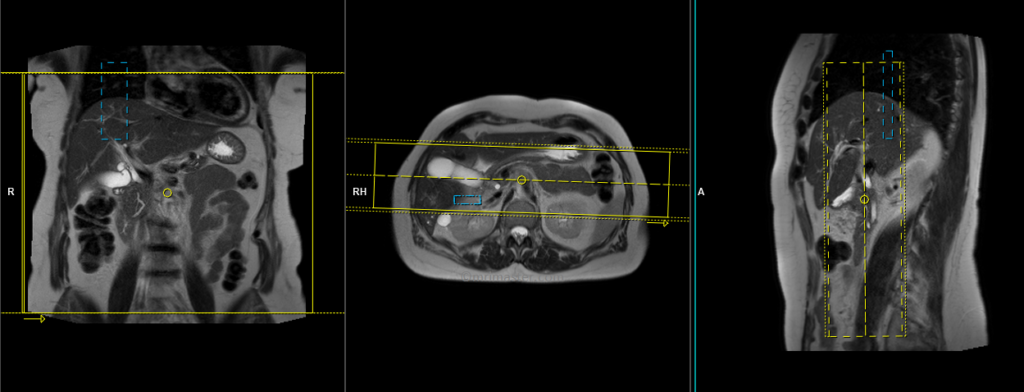

T2 HASTE 5 mm breath hold axial

Plan the axial slices on the coronal breath hold images and position the block horizontally across the liver as shown. Verify the positioning in the other two planes. Establish an appropriate angle in the sagittal plane, aligning it horizontally across the liver. The slices must be sufficient to cover the entire liver from the diaphragm down to the C loop of the duodenum. The phase direction should be from right to left to minimize ghosting artifacts from the anterior abdominal wall. Use phase oversampling to prevent wrap-around artifacts. Instruct the patient to hold their breath during image acquisition. (In our department, we typically instruct patients to take two breaths in and out before providing the “breathe in and hold” instruction.)

TR 2500-3000 | TE 90-110 | FLIP 130 | NEX 1 | SLICE 5MM | MATRIX 256×256 | FOV 350 | PHASE R>L | OVERSAMPLE 50% | TRIGGER NO |